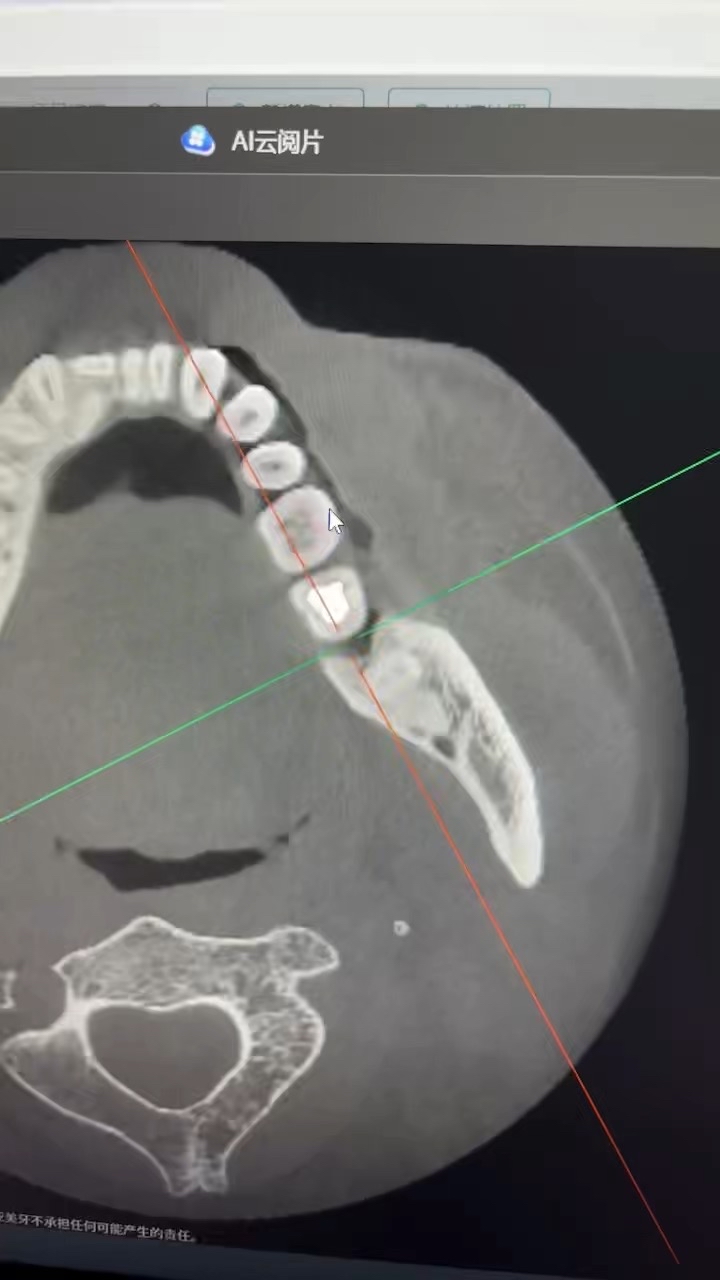

最近又来了几次还是塞牙的问题,患者自己想做冠,但是牙齿1度松动牙周较差,牙齿轻微扣痛,后方还有一颗埋伏度智齿,重新充填后龈上洁治后嘱咐观察

今天来了说肿了补的位置牙线用的过程中掉了一块,口内看可能是牙周脓肿,于是拍了一张根尖片,感觉不是根管引起的瘘管,引流脓液,洁治后,发现近中缺损部位疑似隐裂,拆除充填体发现隐裂贯穿近远中但是裂的位置卡不进探针,再次向下打磨隐裂部位,本来想完全去除隐裂,但没想到裂的还是比较深害怕抗力越来越差,跟患者说可能需要拔除,或者降低咬合后续观察,患者选择降低